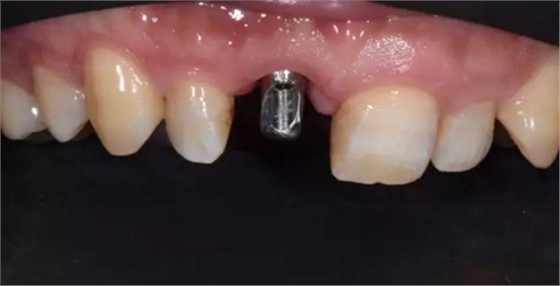

評估C先生身體狀況和口腔內情況后。選擇了種植修復。

種植體植入后